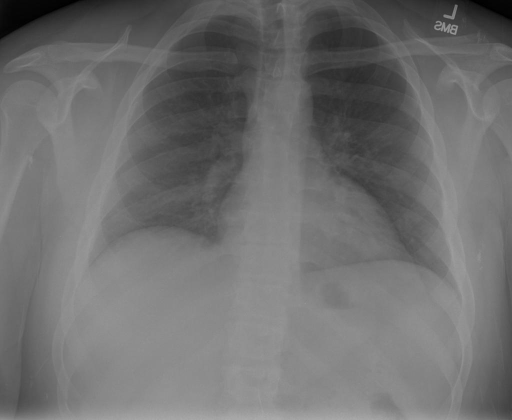

# 本文贡献  - 借助ChatGPT以及公开的数据集,我们构造了一个`X光影像-诊断报告`对的医学多模态数据集; - 我们将构建的中文胸部X光片诊断数据集在[VisualGLM-6B](https://github.com/THUDM/VisualGLM-6B)进行微调训练,并开放了部分训练权重用于学术研究; # 数据集 - [MIMIC-CXR](https://physionet.org/content/mimic-cxr-jpg/2.0.0/)是一个公开可用的胸部X光片数据集,包括377,110张图像和227,827个相关报告。 - [OpenI](https://openi.nlm.nih.gov/faq#collection)是一个来自印第安纳大学医院的胸部X光片数据集,包括6,459张图像和3,955个报告。 在上述工作中,报告信息都为非结构化的,不利于科学研究。为了生成合理的医学报告,我们对两个数据集进行了预处理,并最终得到了可以用于训练的**英文报告**。除此之外,为了更好的支持中文社区发展,借助ChatGPT的能力,我们将英文报告进行了中文翻译,并最终形成了可用于训练的数据集。 |数据集|数量|下载链接| |:-|:-|:-| |MIMIC-CXR-zh|-|-| |OpenI-zh|6,423|[诊疗报告](./data/Xray/openi-zh.json) 、[X光影像](https://pan.baidu.com/s/13GBsDMKf6xBZBSHpoWH_EA?pwd=k9sh)| # 快速上手 1. 安装环境 ```bash # 安装依赖 pip install -r requirements.txt # 国内换源安装依赖 pip install -i https://mirrors.aliyun.com/pypi/simple/ -r requirements.txt ``` 此时默认会安装`deepspeed`库(支持`sat`库训练),此库对于模型推理并非必要,同时部分`Windows`环境安装此库时会遇到问题。 如果想绕过`deepspeed`安装,我们可以将命令改为: ```bash # 安装依赖 pip install -i https://mirrors.aliyun.com/pypi/simple/ -r requirements_wo_ds.txt # 安装SwissArmyTransformer pip install -i https://mirrors.aliyun.com/pypi/simple/ --no-deps "SwissArmyTransformer>=0.3.6" ``` 2. 模型推理 CLI推理: ```python python cli_demo.py --from_pretrained checkpoints/finetune-XrayGLM-05-25-01-04 --prompt_zh '详细描述这张胸部X光片的诊断结果' ``` 更多[参数](https://github.com/WangRongsheng/XrayGLM/blob/main/cli_demo.py#L16) # 效果展示 诊断: |X光影像|诊疗报告(医生)|XrayGLM| |:-|:-|:-| ||根据X射线图像,心脏大小正常,肺部看起来很清晰。已经排除了肺炎、积液、水肿、气胸、腺病、结节或肿块的存在。该发现表明一切正常。换句话说,总体印象是胸部正常。|X光片显示,心脏大小正常。肺部没有气胸或胸腔积液的证据。骨骼结构看起来没有任何异常。总的来说,X光片表明没有发现急性心肺疾病的迹象。| ||X光图片显示没有扭曲的区域、可疑的骨质不透明度或胸腺积液。心脏大小轻微增大,但非常稳定。此外,没有气胸的证据,肺野也正常。总体来说,X光片显示没有急性心脏异常,但要注意轻微的心脏扩大。|X光片显示,心脏大小正常。肺部和纵隔轮廓清晰,没有气胸或胸腔积液的证据。骨骼结构完整,没有任何急性异常。| ||心影形态在正常范围内。没有急性骨质异常。有可能出现没有明显的吸水或肺实质状况的线索。没有大面积积液或气胸。有可能怀疑其有误吸或肺实质问题。为了确诊和治疗,可能需要进行适当的影像学随访。|心脏大小正常,肺部和纵隔轮廓清晰。没有急性异常或活动受限的证据。没有任何明显的气胸、胸腔积液或肺不张的迹象。此外,也没有发现任何局灶性骨质异常或其他急性疾病。| 多轮对话: |X光影像|诊疗报告(医生)| |:-|:-| ||右侧主动脉突出观察到。心脏大小正常。胸部未发现明显的肺气肿、胸膜积液或可疑的肺部病变。报告指出已知右侧主动脉情况正常。| ```bash >> X光影像路径:./data/Xray/861_1.png >> 用户:这是一张什么图? >> XrayGLM:这张图片显示的是一张肺部检查的X光片。 >> 用户:请描述这张胸部X光片的诊断结果 >> XrayGLM:心脏大小正常,肺部清晰。没有急性心肺疾病的证据。 >> 用户:是否存在肺气肿? >> XrayGLM:没有肺气肿。心脏大小正常,肺部清晰。没有发现急性心肺疾病的证据。 >> 用户:平时饮食该注意什么? >> XrayGLM:饮食应该健康,均衡。建议增加蛋白质的摄入量,因为蛋白质有助于维持肌肉和骨骼的健康。多食用蔬菜、水果、全谷物以及健康的脂肪来源如橄榄油、鱼类等可以帮助获得足够的维生素和矿物质。此外,避免过度饮酒或吸烟,这些习惯可能会对心脏健康产生负面影响。 ``` # 项目致谢 1. [VisualGLM-6B](https://github.com/THUDM/VisualGLM-6B)为我们提供了基础的代码参考和实现; 2. [MiniGPT-4](https://github.com/Vision-CAIR/MiniGPT-4)为我们这个项目提供了研发思路; 3. ChatGPT生成了高质量的中文版X光检查报告以支持XrayGLM训练; 4. [gpt_academic](https://github.com/binary-husky/gpt_academic)为文档翻译提供了多线程加速; 5. [MedCLIP](https://github.com/RyanWangZf/MedCLIP) 、[BLIP2](https://huggingface.co/docs/transformers/main/model_doc/blip-2) 、[XrayGPT](https://github.com/mbzuai-oryx/XrayGPT) 等工作也有重大的参考意义;  这项工作由[澳门理工大学应用科学学院](https://www.mpu.edu.mo/esca/zh/index.php)硕士生[王荣胜](https://github.com/WangRongsheng) 、[段耀菲](https://github.com/IsBaSO4) 、[李俊蓉](https://github.com/lijunrong0815)完成,指导老师为檀韬副教授、[彭祥佑](http://www.patrickpang.net/)老师。 *特别鸣谢:[USTC-PhD Yongle Luo](https://github.com/kaixindelele) 提供了有3000美金的OpenAI账号,帮助我们完成大量的X光报告翻译工作 # 免责声明 本项目相关资源仅供学术研究之用,严禁用于商业用途。使用涉及第三方代码的部分时,请严格遵循相应的开源协议。模型生成的内容受模型计算、随机性和量化精度损失等因素影响,本项目无法对其准确性作出保证。即使本项目模型输出符合医学事实,也不能被用作实际医学诊断的依据。对于模型输出的任何内容,本项目不承担任何法律责任,亦不对因使用相关资源和输出结果而可能产生的任何损失承担责任。 # 项目引用 如果你使用了本项目的模型,数据或者代码,请声明引用: ```bash @misc{wang2023XrayGLM, title={XrayGLM: The first Chinese Medical Multimodal Model that Chest Radiographs Summarization}, author={Rongsheng Wang, Yaofei Duan, Junrong Li, Patrick Pang and Tao Tan}, year={2023}, publisher = {GitHub}, journal = {GitHub repository}, howpublished = {\url{https://github.com/WangRongsheng/XrayGLM}}, } ``` # 使用许可 此存储库遵循[CC BY-NC-SA](https://creativecommons.org/licenses/by-nc-sa/4.0/) ,请参阅许可条款。